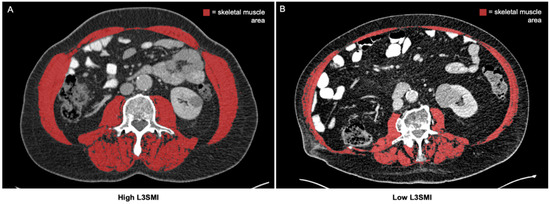

2.2. Assessment of Body Composition and Definition of the Skeletal Muscle Index (L3SMI)

3.2. Assessment of Skeletal Muscle Composition in Patients Receiving ICI Therapy